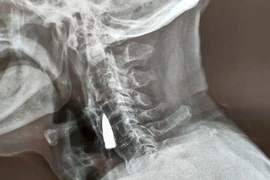

Các bác sĩ chụp X-quang ở Trung Quốc vô cùng sửng sốt khi phát hiện một viên đạn găm trong cổ của một cựu binh quân đội gần 80 năm và ông ấy không hề nhận ra nó còn ở đó.